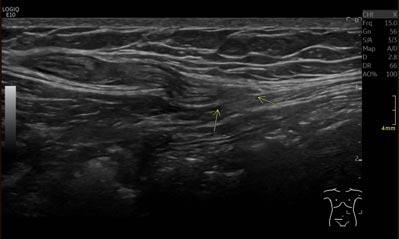

Bij lichamelijk onderzoek wordt een vitale man gezien. Rechts in de onderbuik is in staande positie een zwelling voelbaar die terug te duwen is. Om de aard van deze zwelling verder te duiden, wordt een echo verricht waarop een hernia Spigelii te zien is (zie figuur 1 en 2). Opvallend genoeg lijkt de breukzak zelfs inhoud te bevatten, mogelijk de appendix vermiformis. Een aanvullende CT-scan bevestigt dit beeld (zie figuur 3). Er is geen teken van appendicitis, maar er is wel geïnfiltreerd vetweefsel in de ileocoecaalhoek met een nodulair verdikte lymfeklier.